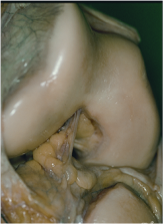

Los cóndilos son convexos tanto en sentido anteroposterior como lateral. Entre ellos son divergentes en sentido posterior estando separados por una escotadura o surco, llamado surco intercondíleo.

Entre los cóndilos femorales y los platillos tibiales se encuentran los meniscos, el interno en forma de C y el externo en forma de O con inserción capsular más laxa y un hiato para el paso del tendón poplíteo, por su morfología y tipo de inserción se lesiona más frecuentemente el menisco interno y las lesiones del externo son mejor toleradas.

Pívot Central: Formado por los ligamentos cruzado anterior y cruzado posterior.

El LCA: Se inserta en la espina tibial anterointerna y sigue un trayecto hacia atrás arriba y hacia fuera para terminar en la cara interna del cóndilo femoral externo. Tiene como función primordial evitar el desplazamiento hacia delante de la tibia respecto al fémur.

El LCP: Se inserta en la espina tibial posteroexterna y sigue un trayecto hacia arriba, delante y adentro para terminar en la cara externa (lateral) del cóndilo femoral interno. Tiene como función primordial evitar el desplazamiento hacia atrás de la tibia respecto al fémur.